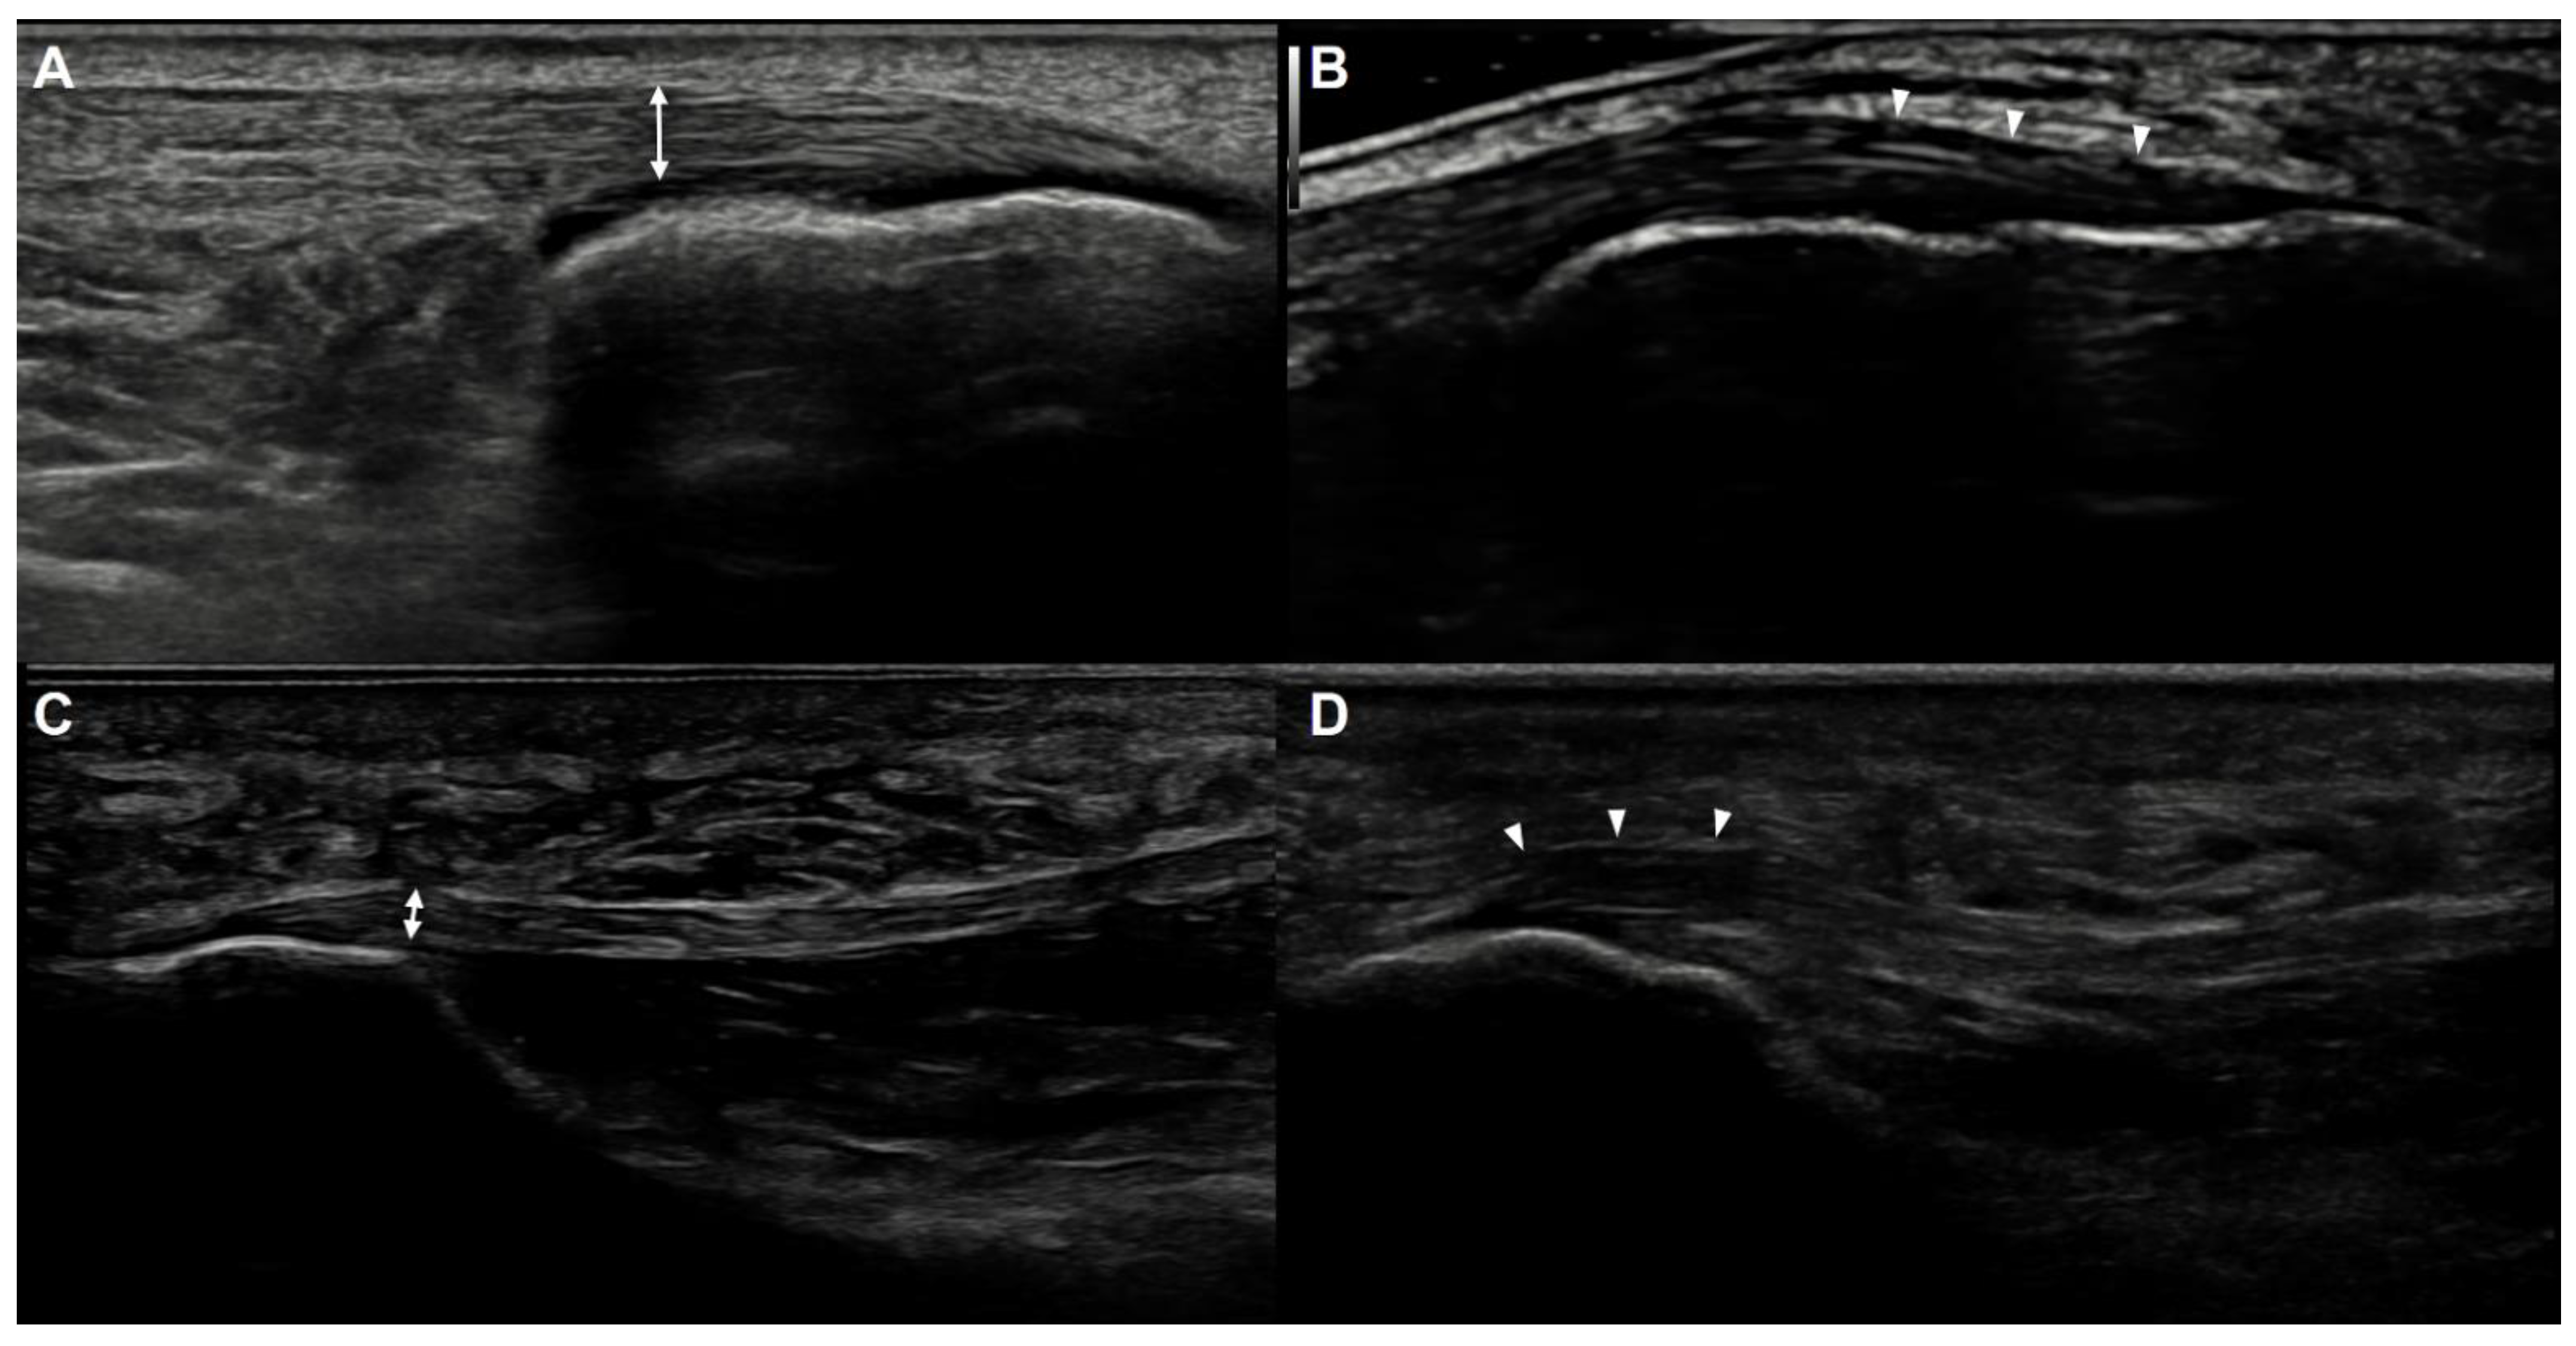

US examinations of all patients were bilaterally performed by a single musculoskeletal specialist with 15 years of experience in musculoskeletal US. A retrospective analysis of US imaging was conducted in consensus by two musculoskeletal US specialists who were blinded to patients’ clinical diagnoses. US examinations were completed using the RS80A ultrasound system with Prestige (Samsung Medison, Co. Ltd., Seoul, Korea) equipped with a 3- to 12-MHz linear transducer. For the US evaluation of the Achilles tendon, patients were positioned lying prone with their ankles hanging free in a neutral position over the edge of the examination table. The thickness of the Achilles tendon was measured within 2 cm of the calcaneal insertion, where the tendon was attached to the bone with a maximal anteroposterior diameter in the long-axis view (Figure 2A). Echogenicity or echotexture was also assessed within 2 cm of the calcaneal insertion, where the tendon was attached to the bone. Abnormal echogenicity of the Achilles tendon was defined as hypoechoic area evident in both the longitudinal and transverse scans and heterogeneous appearance of the fibrillar pattern (Figure 2B). For the US evaluation of the plantar fascia, patients were positioned lying prone with their ankles hanging free in a slightly plantarflexed position. Plantar fascia thickness was measured as the maximal anteroposterior diameter in the long-axis view at its thickest point within 1 cm of the calcaneal attachment [6,7] (Figure 2C) and echogenicity was assessed around the medial tubercle of the calcaneus. Abnormal echogenicity of the plantar fascia was defined as hypoechoic area evident in both the longitudinal and transverse scans and heterogeneous appearance of the fibrillar pattern (Figure 2D). To confirm the difference between hypoechoic area and anisotropy, the examiner attempted to keep the direction of the beam as close to perpendicular as possible in relation to the structures in question using the techniques such as toggling the transducer and heel-to-toe rocking.

Figure 2.

Ultrasonographic measurement of the thickness of the Achilles tendon and plantar fascia. (A) The maximal thickness of the insertional area of the Achilles tendon (two-sided arrow) was measured within 2 cm of the calcaneal insertion, where the tendon is attached to the bone. (B) A hypoechoic area and loss of the fibrillar pattern (arrowheads) were evident at the insertional area of the Achilles tendon. Note the toggling technique to keep the direction of the beam as close to perpendicular as possible in relation to the insertional area of the Achilles tendon was used. (C) The maximal thickness of the plantar fascia (two-sided arrow) was measured within 1 cm of the calcaneal attachment. (D) A hypoechoic area and loss of the fibrillar pattern (arrowheads) were evident at the attachment site of the plantar fascia.